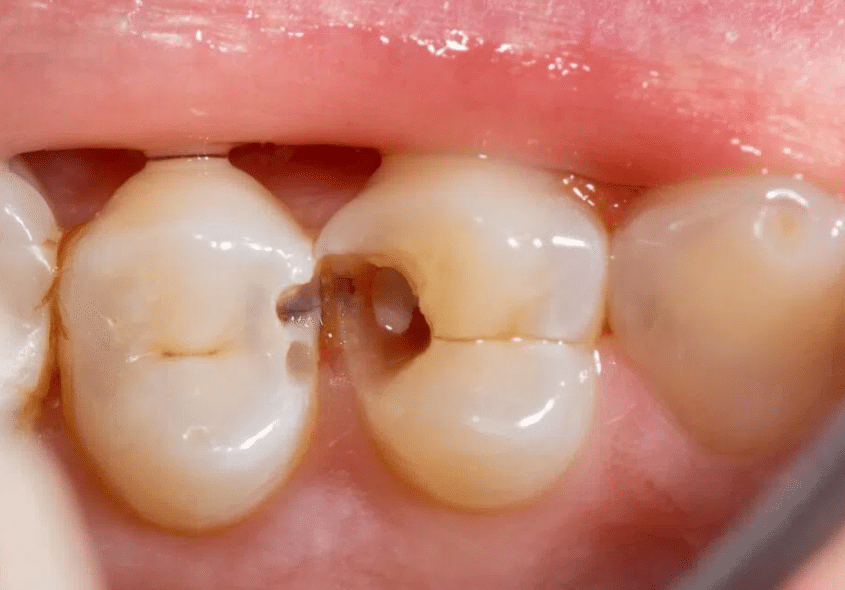

Plaque and bacteria play pivotal roles in dental caries formation. This section explores the intricate process of acidic erosion leading to enamel decay, laying the foundation for the subsequent discussion on treatment options with Siri Dental Hospital.

Dental caries manifest in various stages, each requiring distinct treatment approaches. From the early formation of white spots to advanced stages involving pulp, understanding these categories is essential for tailoring effective treatments at Siri Dental Hospital.